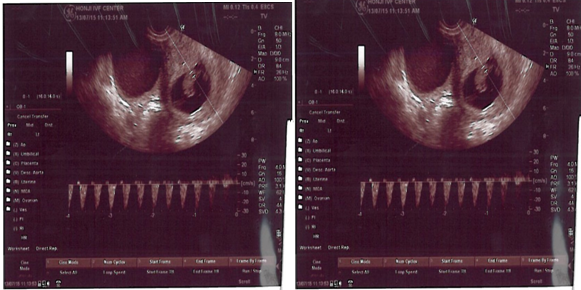

今回は張先生の優れた手術、実験室チームの良好な品質管理、妊娠初期の少量での正確な薬品とデータ制御により、私達はついに妊娠できたのです。心臓の鼓動を耳にした瞬間、私達には生命の意義が深く刻み込まれました!そして縁というものは予想外の時に不思議なめぐり合わせをするものだ、と悟ったのです!